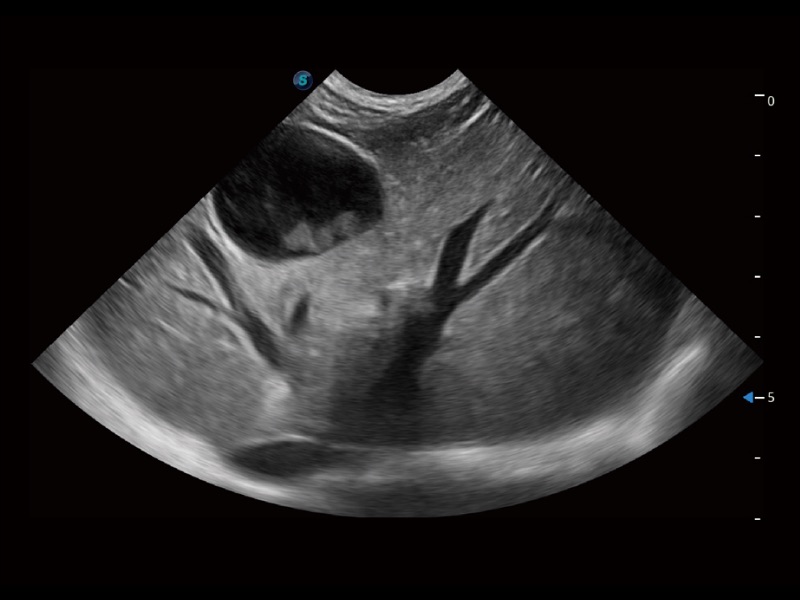

大型犬、马科、农场动物及大型异宠动物

ProPet 70 全新的动物超声智能软件和丰富的探头群,为动物医生提供了高清晰度和精细分辨率的图像,无论在宠物、马科、畜牧还是实验室动物等应用中都可以轻松应对,为您的日常工作带来满意的体验。